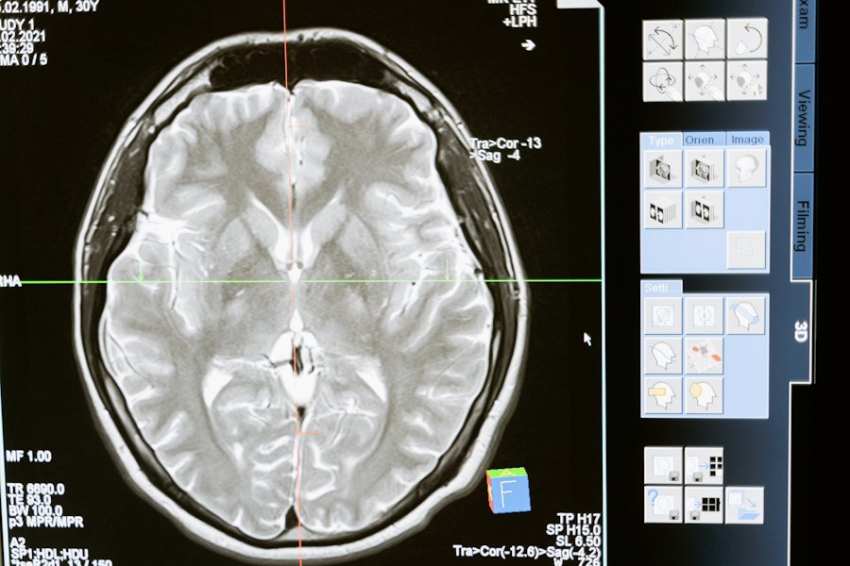

Магнитно-резонансная томография представляет собой современный метод диагностики, широко применяемый в медицине. Важно отметить, что данный метод не связан с использованием рентгеновского либо ионизирующего излучения, которое требует осторожности в частом применении.